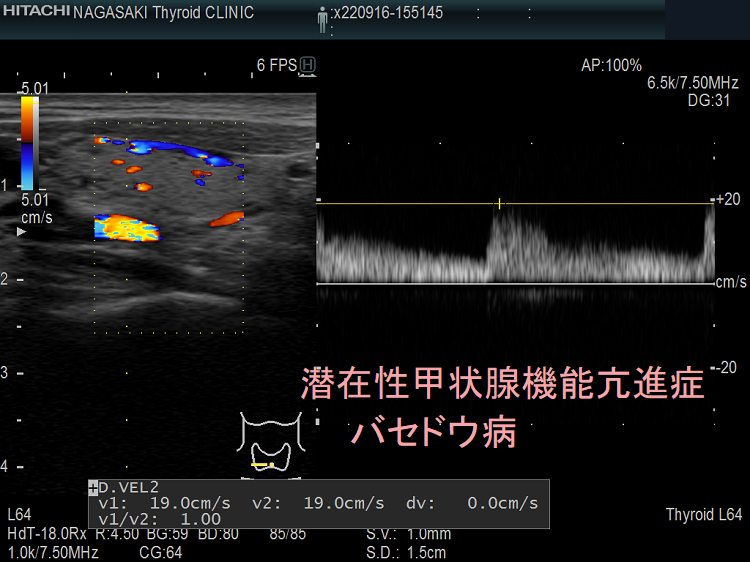

潜在性甲状腺機能亢進症は、甲状腺刺激ホルモン (TSH) レベルが低いか検出できないが、甲状腺ホルモンレベルは健康なままである場合です。通常は無症状であり、治療が必要ない場合もあります。

潜在性甲状腺機能亢進症の人では、甲状腺は正常レベルの T4 と T3 を生成します。しかし、彼らのTSHレベルは通常よりも低いです。このホルモンバランスの乱れが症状を引き起こします。

バセドウ病による潜在性甲状腺機能亢進症がある場合は、治療が必要です。医師はおそらく放射性ヨウ素療法またはメチマゾールなどの抗甲状腺薬を処方するでしょう。